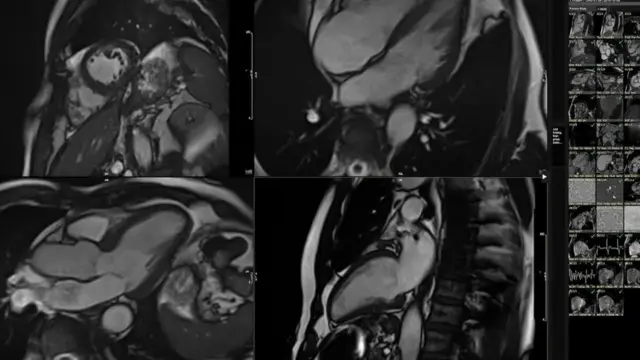

Жараёнда жисмоний машғулотдан сўнг юракни МРТ қилиш ҳам бор эди.

Тизим менинг МРТ тасвиримда олинган 3D даги юзлаб тафсилотларни таҳлил қилди ва уларни соғлом ҳаёт кечирган ва турли ёшдаги 5000 нафар одамнинг юрак тасвирлари билан қиёслади.